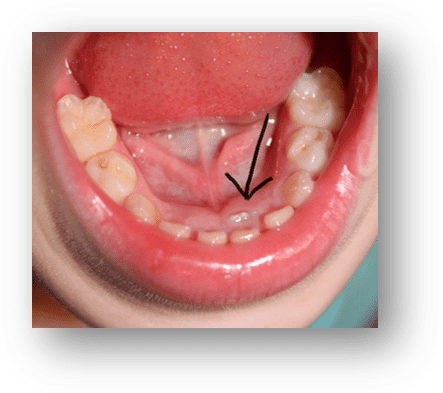

Lower Incisor Crowding

It can be exciting for children to start getting their first wriggly teeth. It will be the lower front teeth in the middle, usually between 5-6 years old. But to the concern of many parents, they have a look only to see the adult incisors coming up on the inside of...